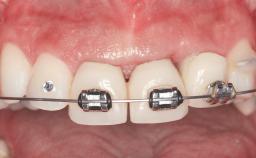

This 20-year-old woman was referred to our department in July 2006. Four months earlier, she had experienced dental trauma to the anterior maxilla when traveling in South America. The emergency treatment included emergency root canal treatment of teeth 12 and 11. Tooth 21 was also subjected to endodontic treatment later. At the initial examination, the patient was not in pain but reported increased mobility of tooth 12. The clinical examination revealed a high smile line, medium thickness of the soft tissue, and rectangular tooth forms. Discoloration of tooth 12 was evident. The periapical radiograph provided by the referring dentist indicated a fracture line at both teeth 12 and 11. A cone-beam computed tomography (CBCT) scan confirmed these fractures. No pathology was found to be associated with tooth 21.

Prosthesis Type FDP

Loading Protocol Conventional or early

Retention Screw-retained, with 2 unsplinted implants Screw-retained, with 2 unsplinted implants